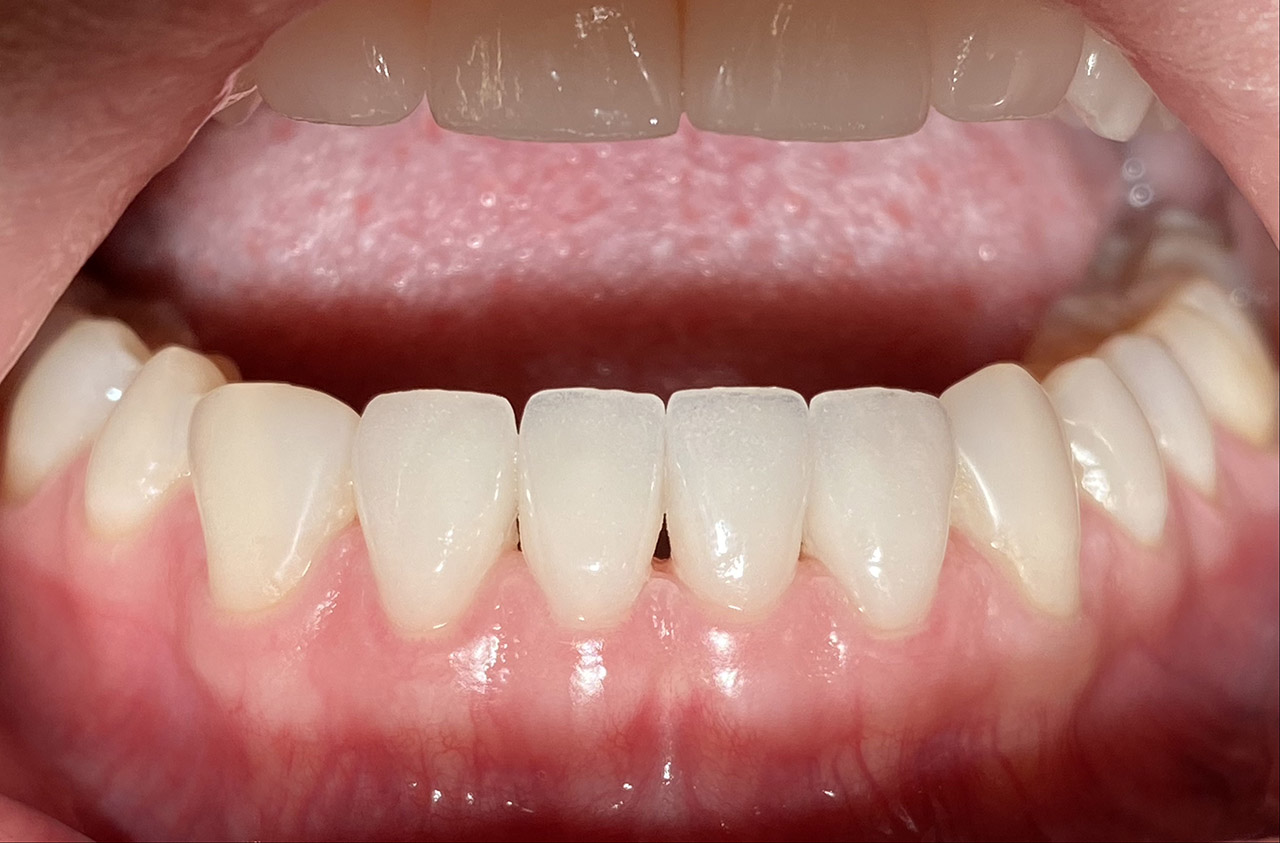

Aplasien/Nichtanlagen, dadurch bleibende Milchzähne, Diasteme/Zahnlücken,

Bleaching/Bleichen, Positionierung der Zähne/Kieferorthopädie (Dr. Maija Eltz), Verblendung mit Veneers/Keramikschalen.